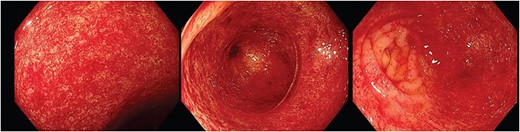

Given initial biochemical markers suggested a significant bleeding diathesis (Hemoglobin 55 g/L(Reference (120–160 g/L).); low platelets (88 × 109/ L)(Reference (150–450 x 109/L).); elevated INR (1.5)(Reference (<1.0).); and normal liver function tests, urea and inflammatory markers), she was taken for a computed tomography (CT)-angiogram of the abdomen and pelvis. A focus of active bleeding on all phases was not found with the radiologist reporting non-specific porta hepatis oedema without any evidence of cirrhosis, intrabdominal ascites, or vascular thrombus (Fig. 1). Despite adequate medical optimisation and blood transfusions the next day she collapsed and deteriorated acutely due to a presumed acute bleed, given her CT head was unremarkable. After intense resuscitation, the patient was taken to theater emergently where the gastroscopic findings were unremarkable and varices were not identified, whereas the colonoscopy found significant severe inflammation, a large adherent blood clot, congestion (oedema) and caecal erythema (Fig. 2). At this time, the radiologist’s report for the liver ultrasound performed immediately before the endoscopic procedures confirmed a new diagnosis of liver cirrhosis. After adequate further medical investigation and optimisation of her liver cirrhosis, an iron transfusion and 3 days of a continuous octreotide infusion, she went home for further outpatient management of her liver disease without any further stigmata of bleeding to date.

Endoscopic images depicting macroscopic findings of PHC including vascular ectasias and nonspecific inflammatory mucosal changes leading to friable mucosa which bled on contact.

Figure 2 depicts the macroscopic findings encountered that led to this exceptional diagnosis of PHC by an experienced endoscopist. The endoscopic mucosal changes are non-specific inflammation and subtle vascular changes, which are important features described in literature [1]. These were noted by the histopathologist microscopically but were unable to provide a diagnosis. This scenario often presents many endoscopists and histopathologists a significant challenge as the variations in endoscopic descriptions and the absence of uniform diagnostic criteria/classifications in literature can make a definitive diagnosis especially difficult. In these cases, clinicians often rely on patient history to identify a possible underlying cause for the endoscopic findings, such as alcohol misuse.